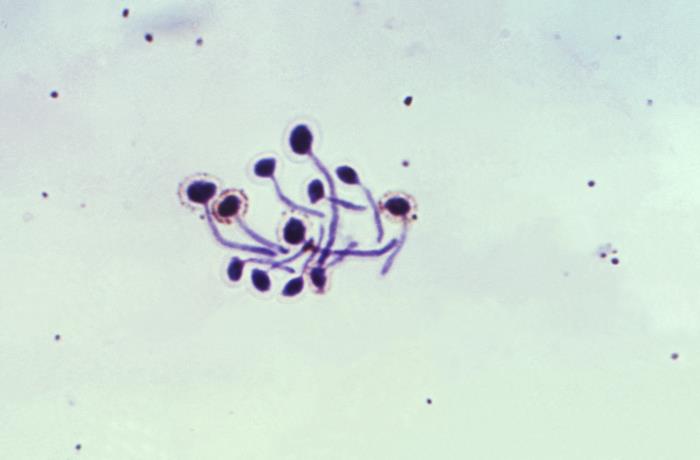

顯微鏡下的白假絲酵母菌

白假絲酵母菌屬于念珠菌屬又稱為白色念珠菌。念珠菌屬有270余種,其中的10個種有致病性。白假絲酵母菌是本屬最常見的致病菌,可引起皮膚、口腔、黏膜和內(nèi)臟的急、慢性感染,即假絲酵母菌病。那么如何檢測白假絲酵母菌?可以采用培養(yǎng)基和顯微鏡檢查法。

二、顯微鏡檢查法

在生物顯微鏡下,菌體呈無色透明,但具有高折光反射,使其易于識別。圓形或卵圓形,直徑3-6μm,革蘭染色陽性,著色不均,以芽生方式繁殖。

綜上所述,通過生物顯微鏡作為真菌學(xué)實驗中的核心工具,不僅用于白假絲酵母菌的觀察,還廣泛應(yīng)用于其他真菌的鑒定和診斷。通過顯微鏡觀察,可以了解真菌的菌落形態(tài)、生長特點以及細(xì)胞形態(tài)等關(guān)鍵信息,為真菌學(xué)研究和臨床實踐提供有力支持。